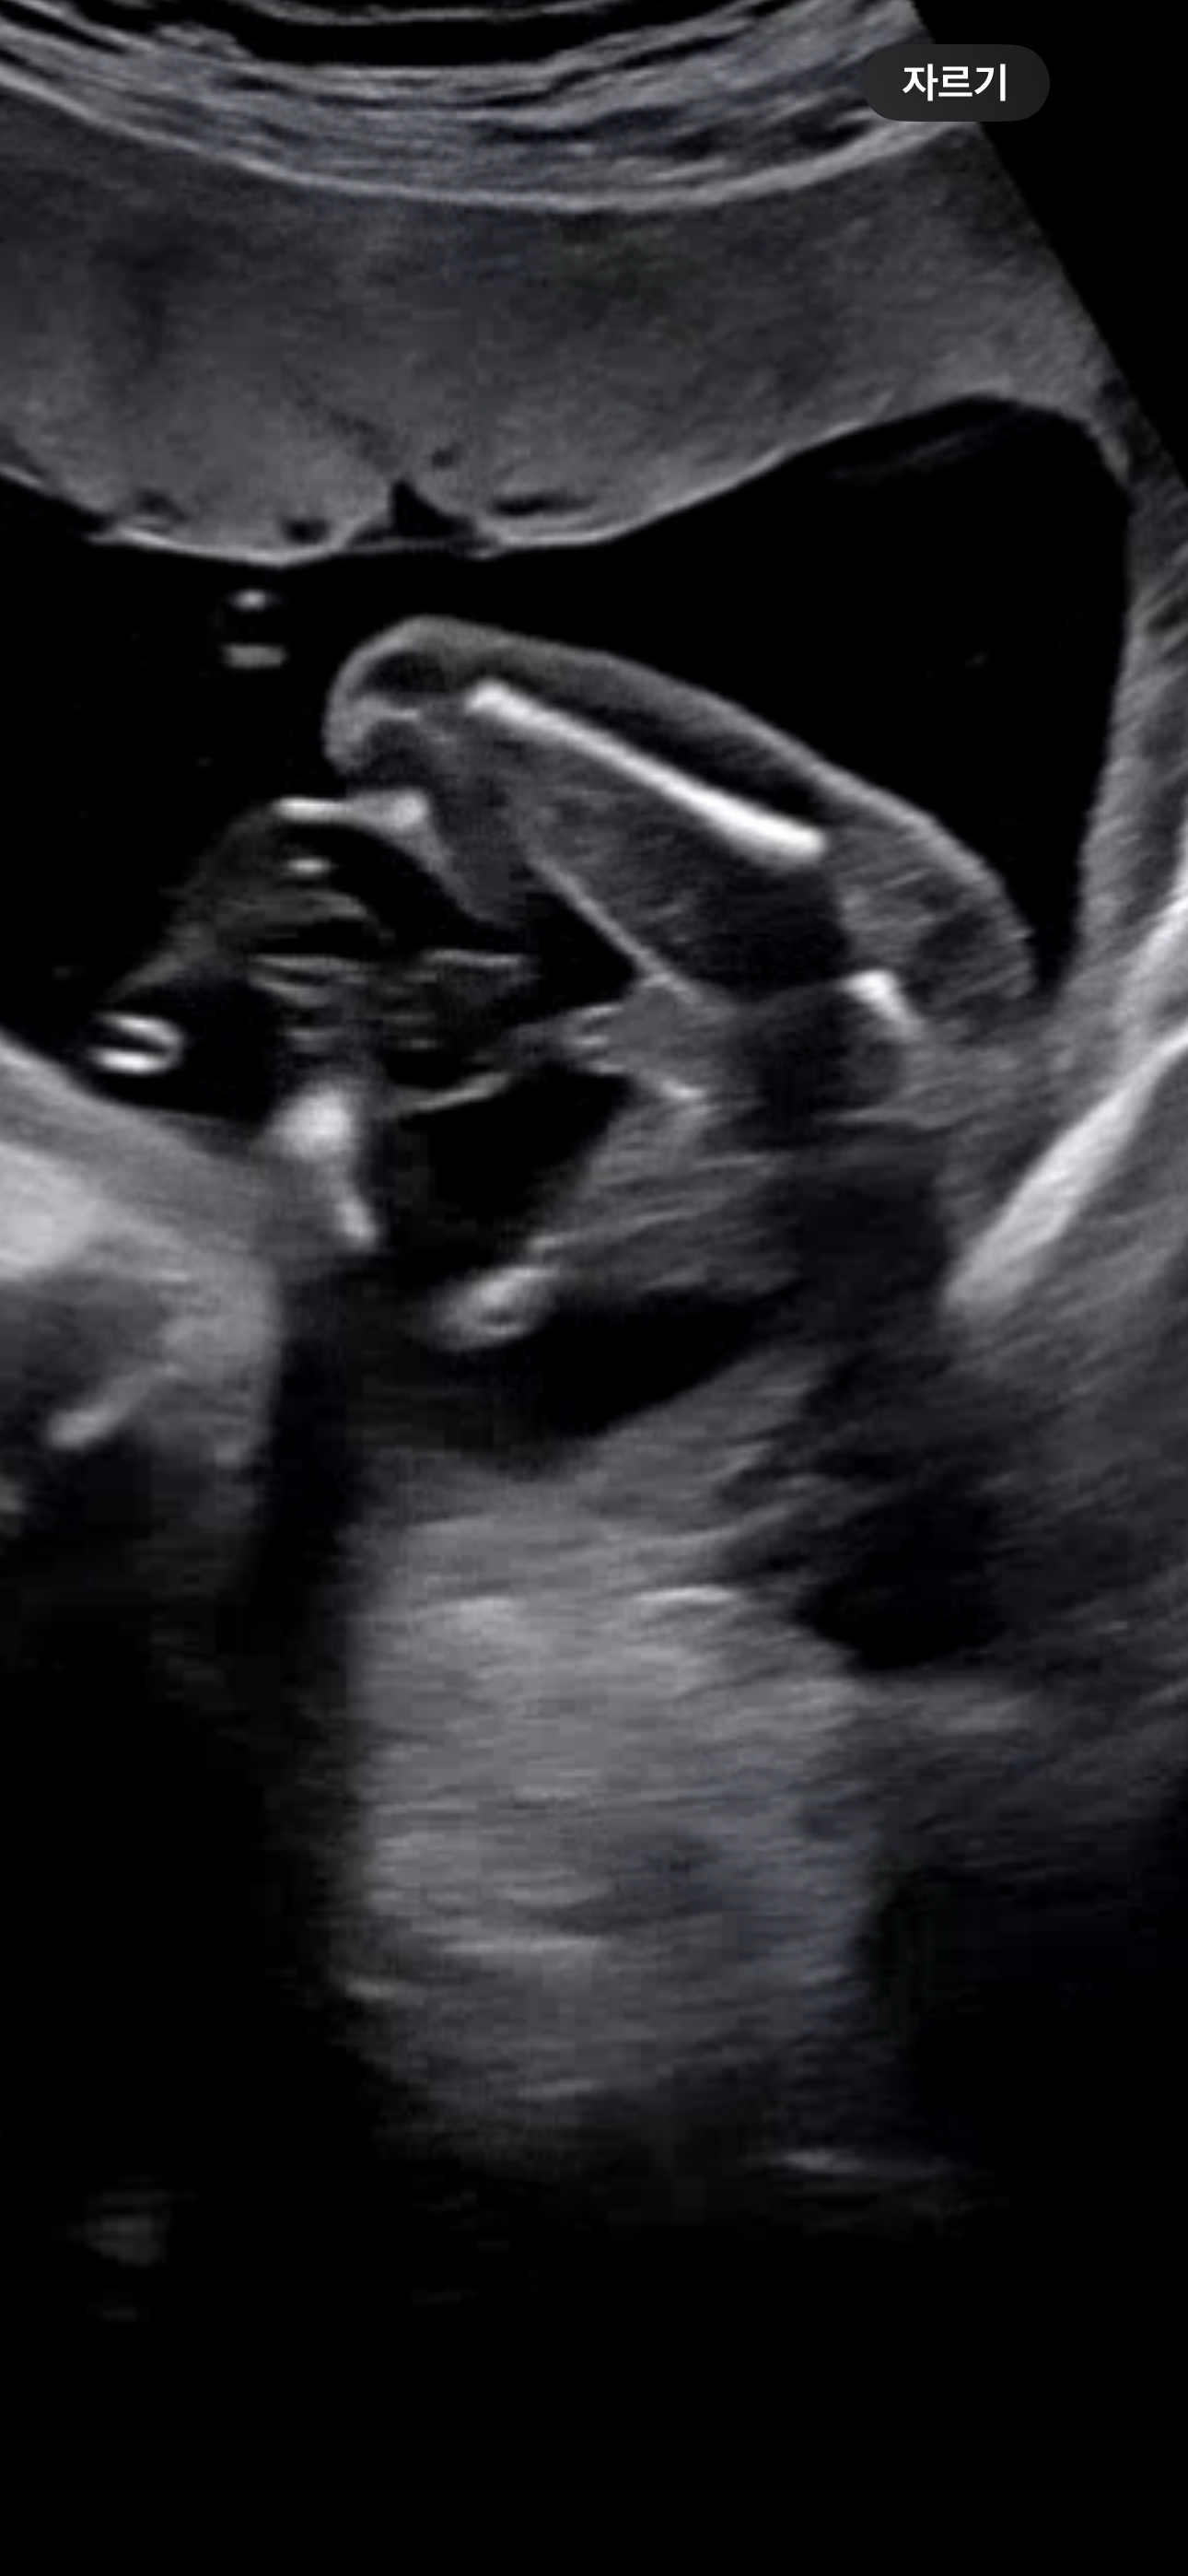

아들 초음파

첫째때는 이렇개 크지 않았는데 둘찌 18주 초음파 🌶️는 길고 커서 탯줄인지🌶️인지 모르겠네.. 다른 아들맘들 댓글달아줘ㅠㅠ

저딸인데 탯줄은 엉덩이라인이랑 같이 보일수가 없더라구요 엉덩이뒷라인이 사라져야 탯줄이 보였어요!

음낭이있어서... 아들확실입니당